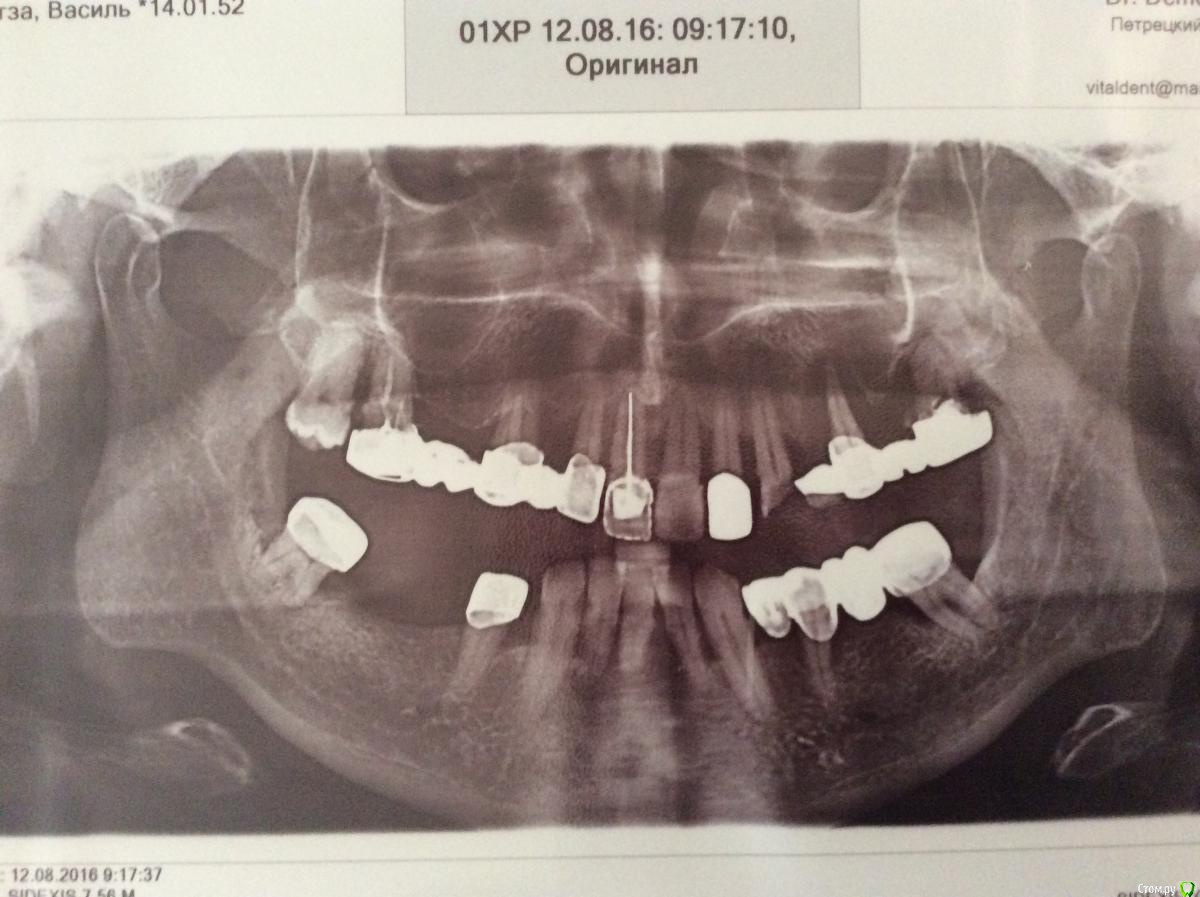

dr.Dre Опубликовано 15 августа, 2016 Поделиться Опубликовано 15 августа, 2016 Добрый день ,коллеги как поступить в данной ситуации,можно ли поставить мк 33 - 38? Ссылка на комментарий

TIGER Опубликовано 15 августа, 2016 Поделиться Опубликовано 15 августа, 2016 всё в плевательницу...импланты в зависимости от бюджета...зубы не жильцы 1 Ссылка на комментарий

RuStom Опубликовано 15 августа, 2016 Поделиться Опубликовано 15 августа, 2016 Откуда там 38, там же 7-кой вроде заканчивается?Иля я не правильно понимаю?Если бюджетно - то съемники после хирургич, пародонтологич и терапетич санации Ссылка на комментарий

Аслан Опубликовано 15 августа, 2016 Поделиться Опубликовано 15 августа, 2016 (изменено) оставить внизу два клыка, остальное вообще все на вынос, через две недели снять швы и слепок под протезы, через месяца полтора два сделать или перебазировку или два новых протеза. дополнить можно имплантами 44-42-32-34 и на них или балку или шарики, клыки удалить на этапе протезирования имплантов Изменено 15 августа, 2016 пользователем Аслан Ссылка на комментарий